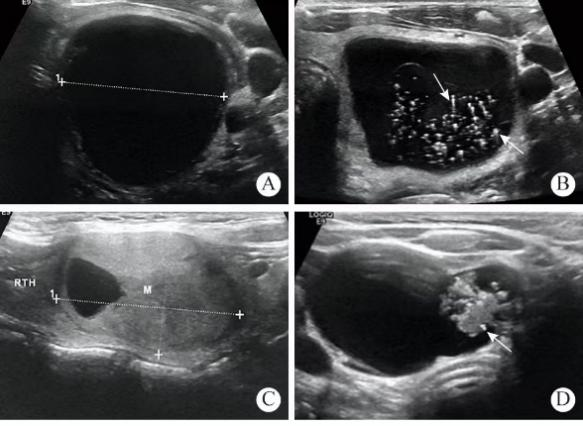

甲状腺结节超声

2. 超声检查(首选)

o 测量结节大小(>1cm需重点关注)

l评估TI-RADS分级:▫ 2类(良性,恶性风险<2%)▫ 4类(可疑恶性,风险5-80%)▫ 5类(高度恶性可能,风险>80%)

4. 细针穿刺活检(FNAB)适用于TI-RADS 4类以上或>1.5cm结节,诊断准确率>95%